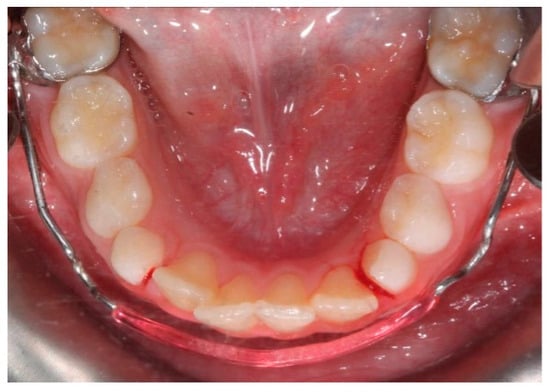

The lower jaw is considered the guiding arch in crowding therapy because it is difficult to modify its perimeter due to the more compact bone structure and the continuity with the mandibular branch, which does not allow for distalization [37,41]. In addition, the symphysis cartilage ossifies in the first year of life, so it is not possible to perform an orthopedic bone expansion, as in the upper jaw, working at the level of the median palatine suture [41,42]. The modalities of space recovery in mixed dentition are: arch perimeter increment, reduction in mesiodistal widths of teeth and serial extractions [2,43,44]. In the upper arch, the expansions are quite stable, but inferiorly, it is universally recognized that the expansion of the intercanine diameter always recurs, whereas expansion at the molar level is quite stable, which should be considered [27,45,46,47]. The space that can be recovered in the lower arch depends on the type of sector: in general, in the posterior sector, utilizing a lip bumper-style device, it is possible to recover a maximum of 2 mm of space per molar distalization in the posterior regions. At the molar level in the lateral sectors, the arch length could increase by about 0.4 mm; at the canine level, the arch length increases about 0.7 mm [48]. The vestibularization of one millimeter of the incisal margin in the anterior sector results in the gain of one millimeter of arch space, or roughly a ratio of one to one (changing the arch form) [47]. Schwarz’s appliance (Figure 3) and lip bumper (Figure 4) are two commonly used appliances for increasing lower dental arch dimensions [49]. In their study, Vincenzo Quinzi et al. compared the effects of these appliances on reducing mandibular crowding by increasing lower arch dimensions [27]. The study included twenty subjects (10 males and 10 females). Ten patients were treated with Schwarz’s appliance, and ten with lip bumper. The Schwarz appliance was more effective in increasing intercanine arch dimensions and arch perimeter, although the lip bumper reached a greater increase in arch length [27]. Since the 1970s, there have been reports of spontaneous changes in mandibular dentition caused by maxillary expansion [31,50]. Di Ventura et al. assessed the consequences of rapid maxillary expansion (RME) anchored to primary molars on the mandibular arch. A total of 54 patients were recruited for this study and divided into two groups: a test group (21 patients, 7.4 ± 1.2 years) who underwent RME, and a control group (17 patients, 7.3 ± 1.1 years old) who did not receive any treatment. The results of this study showed a significant increase in interdental width in the lower arch after 9 months of RME therapy [31]. Olivia Griswold et al. evaluated the changes in sagittal mandibular incisors’ position in response to lip bumper therapy using CBCT [32]. In this study, the authors compared a group that was treated only with rapid maxillary expansion (experimental group) and an RME + LB (lip bumper) group (control group) [32]. The CBCTs were placed in 3D on the mandibular structure, and the angular and linear alterations in the mandibular incisors throughout LB therapy were assessed. In the investigation, there was no statistically significant difference in the degree of mandibular incisor protrusion between the two groups; the lip bumper did not generate substantial proclination, protrusion or extrusion of the mandibular incisors. [13]. Air-rotor stripping (ARS) (Figure 5) is a technique for creating space during the mixed dentition period by reducing interproximal enamel thickness. Yahya B. Nakhjavani et al. assessed the efficacy of the mesial stripping of mandibular deciduous canines for the correction of rotated and lingually erupted lateral incisors in 42 patients with <3 mm mandibular crowding [33]. In this study, the mesial stripping of mandibular primary canines resulted in full crowding correction; in just few cases, the amount of crowding did not reach zero, and a small crowding in the range of 0.06 to 0.1 mm remained [33]. The extraction of all the first premolars with subsequent orthodontic treatment is the most used method to relieve dental crowding [51]. The importance and timing of extraction as a component of orthodontic therapy for late incisor crowding have been well investigated [35]. No difference in late incisor crowding is shown by the data, regardless of whether serial extraction or early or late premolar extraction is performed prior to orthodontic treatment. Additionally, selecting a non-extraction orthodontic procedure has been linked to post-retention crowding [35]. Maurits Persson et al. investigated changes in the mandibular incisor area from early adolescence to late adulthood in patients with a class I crowding malocclusion treated in the mixed dentition by the extraction of all first premolars without subsequent orthodontic treatment [35]. The extraction group included 24 subjects who had all their first premolars extracted at a mean age of about 11.5 years to treat a class I space deficiency malocclusion. The control group included 21 subjects who had normal occlusions at the age of 13 years [35]. The extraction group showed no improvements in lower incisor irregularity, and a significant increase in lower tooth space insufficiency into adulthood. Lower incisor irregularity and space shortage developed significantly in the control group throughout late adulthood [35]. Premolar extraction is the sole treatment option for severe crowding in a class I occlusion, allowing for spontaneous adjustments and more stable incisor alignment in late adulthood, according to the authors [35] (Table 2).

Figure 4. Lip bumper.